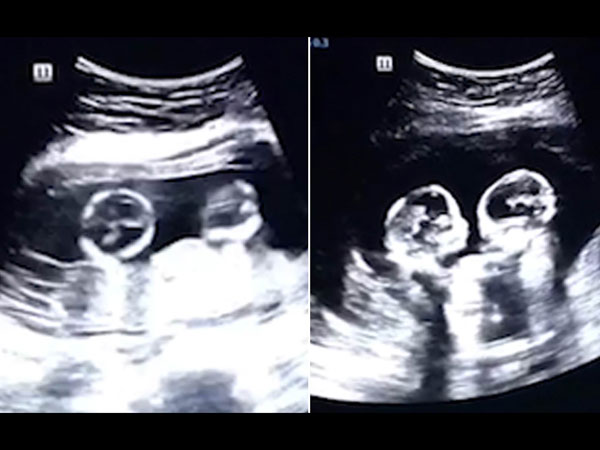

ബോക്സിംഗുമായാണ് ഇത്തരത്തിലുള്ള ഈ ഗര്ഭസ്ഥശിശുക്കളുടെ തല്ലിനെ അവരുടെ അച്ഛന് സാദൃശ്യപ്പെടുത്തിയിരുക്കുന്നത്. എന്നാല് ഇത് ഇന്ന് സോഷ്യല് മീഡിയയില് തരംഗമായിരിക്കുകയാണ് എന്നതാണ് സത്യം. പലരും അത്ഭുതത്തോടെ തന്നെയാണ് ഇത് കാണുന്നതും.

വയറ്റില് വെച്ച് തന്നെ ഇങ്ങനെ

വയറ്റില് വെച്ച് തന്നെ ഇത്തരത്തില് അടിയാണെങ്കില് പുറത്ത് വന്നാല് എന്തായിരിക്കും എന്നാണ് പലരും അഭിപ്രായം പറയുന്നത്. രണ്ട് പെണ്കുട്ടികളാണ് ഇവര്ക്ക് ജനിച്ചത്. 2.5 മില്ല്യണ് വ്യൂസ് 80000 കമന്റുകളാണ് ഈ വീഡിയോക്ക് ലഭിച്ചിരിക്കുന്നത്. രസകരമായ ഈ വീഡിയോ ഇന്ന് യൂട്യൂബിലും സോഷ്യല് മീഡിയയിലും ഇന്ന് ട്രെന്ഡിങ്ങില് ഒന്നാമതാണ്.